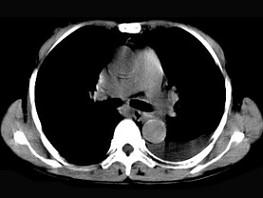

问题 女,55岁,胸痛伴咯血丝痰一周,胸部CT如图,最可能的诊断为 ( )

选项 A、多发性肺脓肿 B、结节病 C、左侧周围型肺癌并肺内转移 D、左侧中央型肺癌并肺内转移 E、转移性肺癌

答案 C